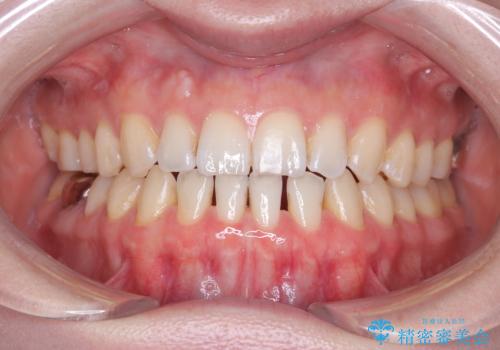

すきっ歯・切端咬合・空隙歯列|インビザラインで11ヵ月で治療完了

- すきっ歯と切端咬合(上下の前歯が先端で当たるかみ合わせ)を主訴にご来院された患者様です。

矯正検査を行った結果、非抜歯でインビザラインによる治療が可能と判断し、マウスピース矯正で改善を行いました。

11ヵ月で矯正治療が終了し、前歯の隙間も改善、見た目とかみ合わせも良好な状態となり、患者様にも大変ご満足いただけました。